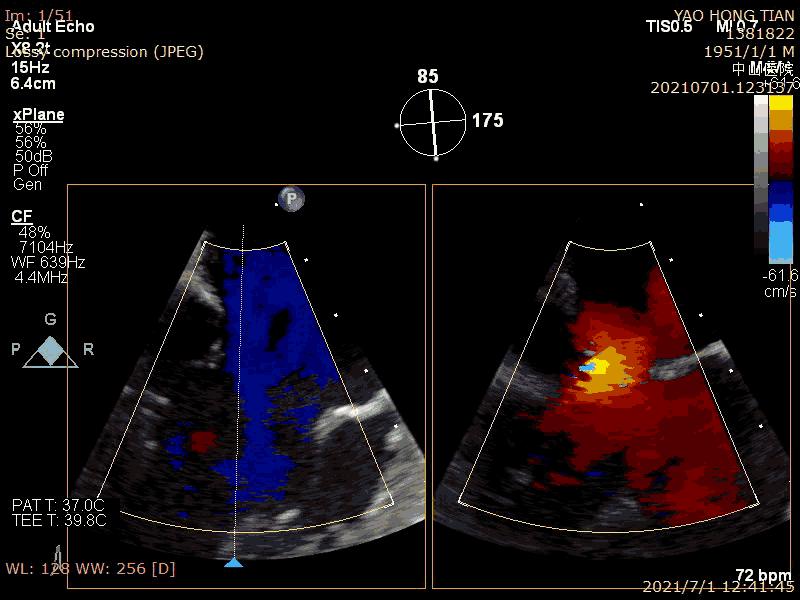

最后效果(轻微反流),最大/平均压:差4/1mmHg